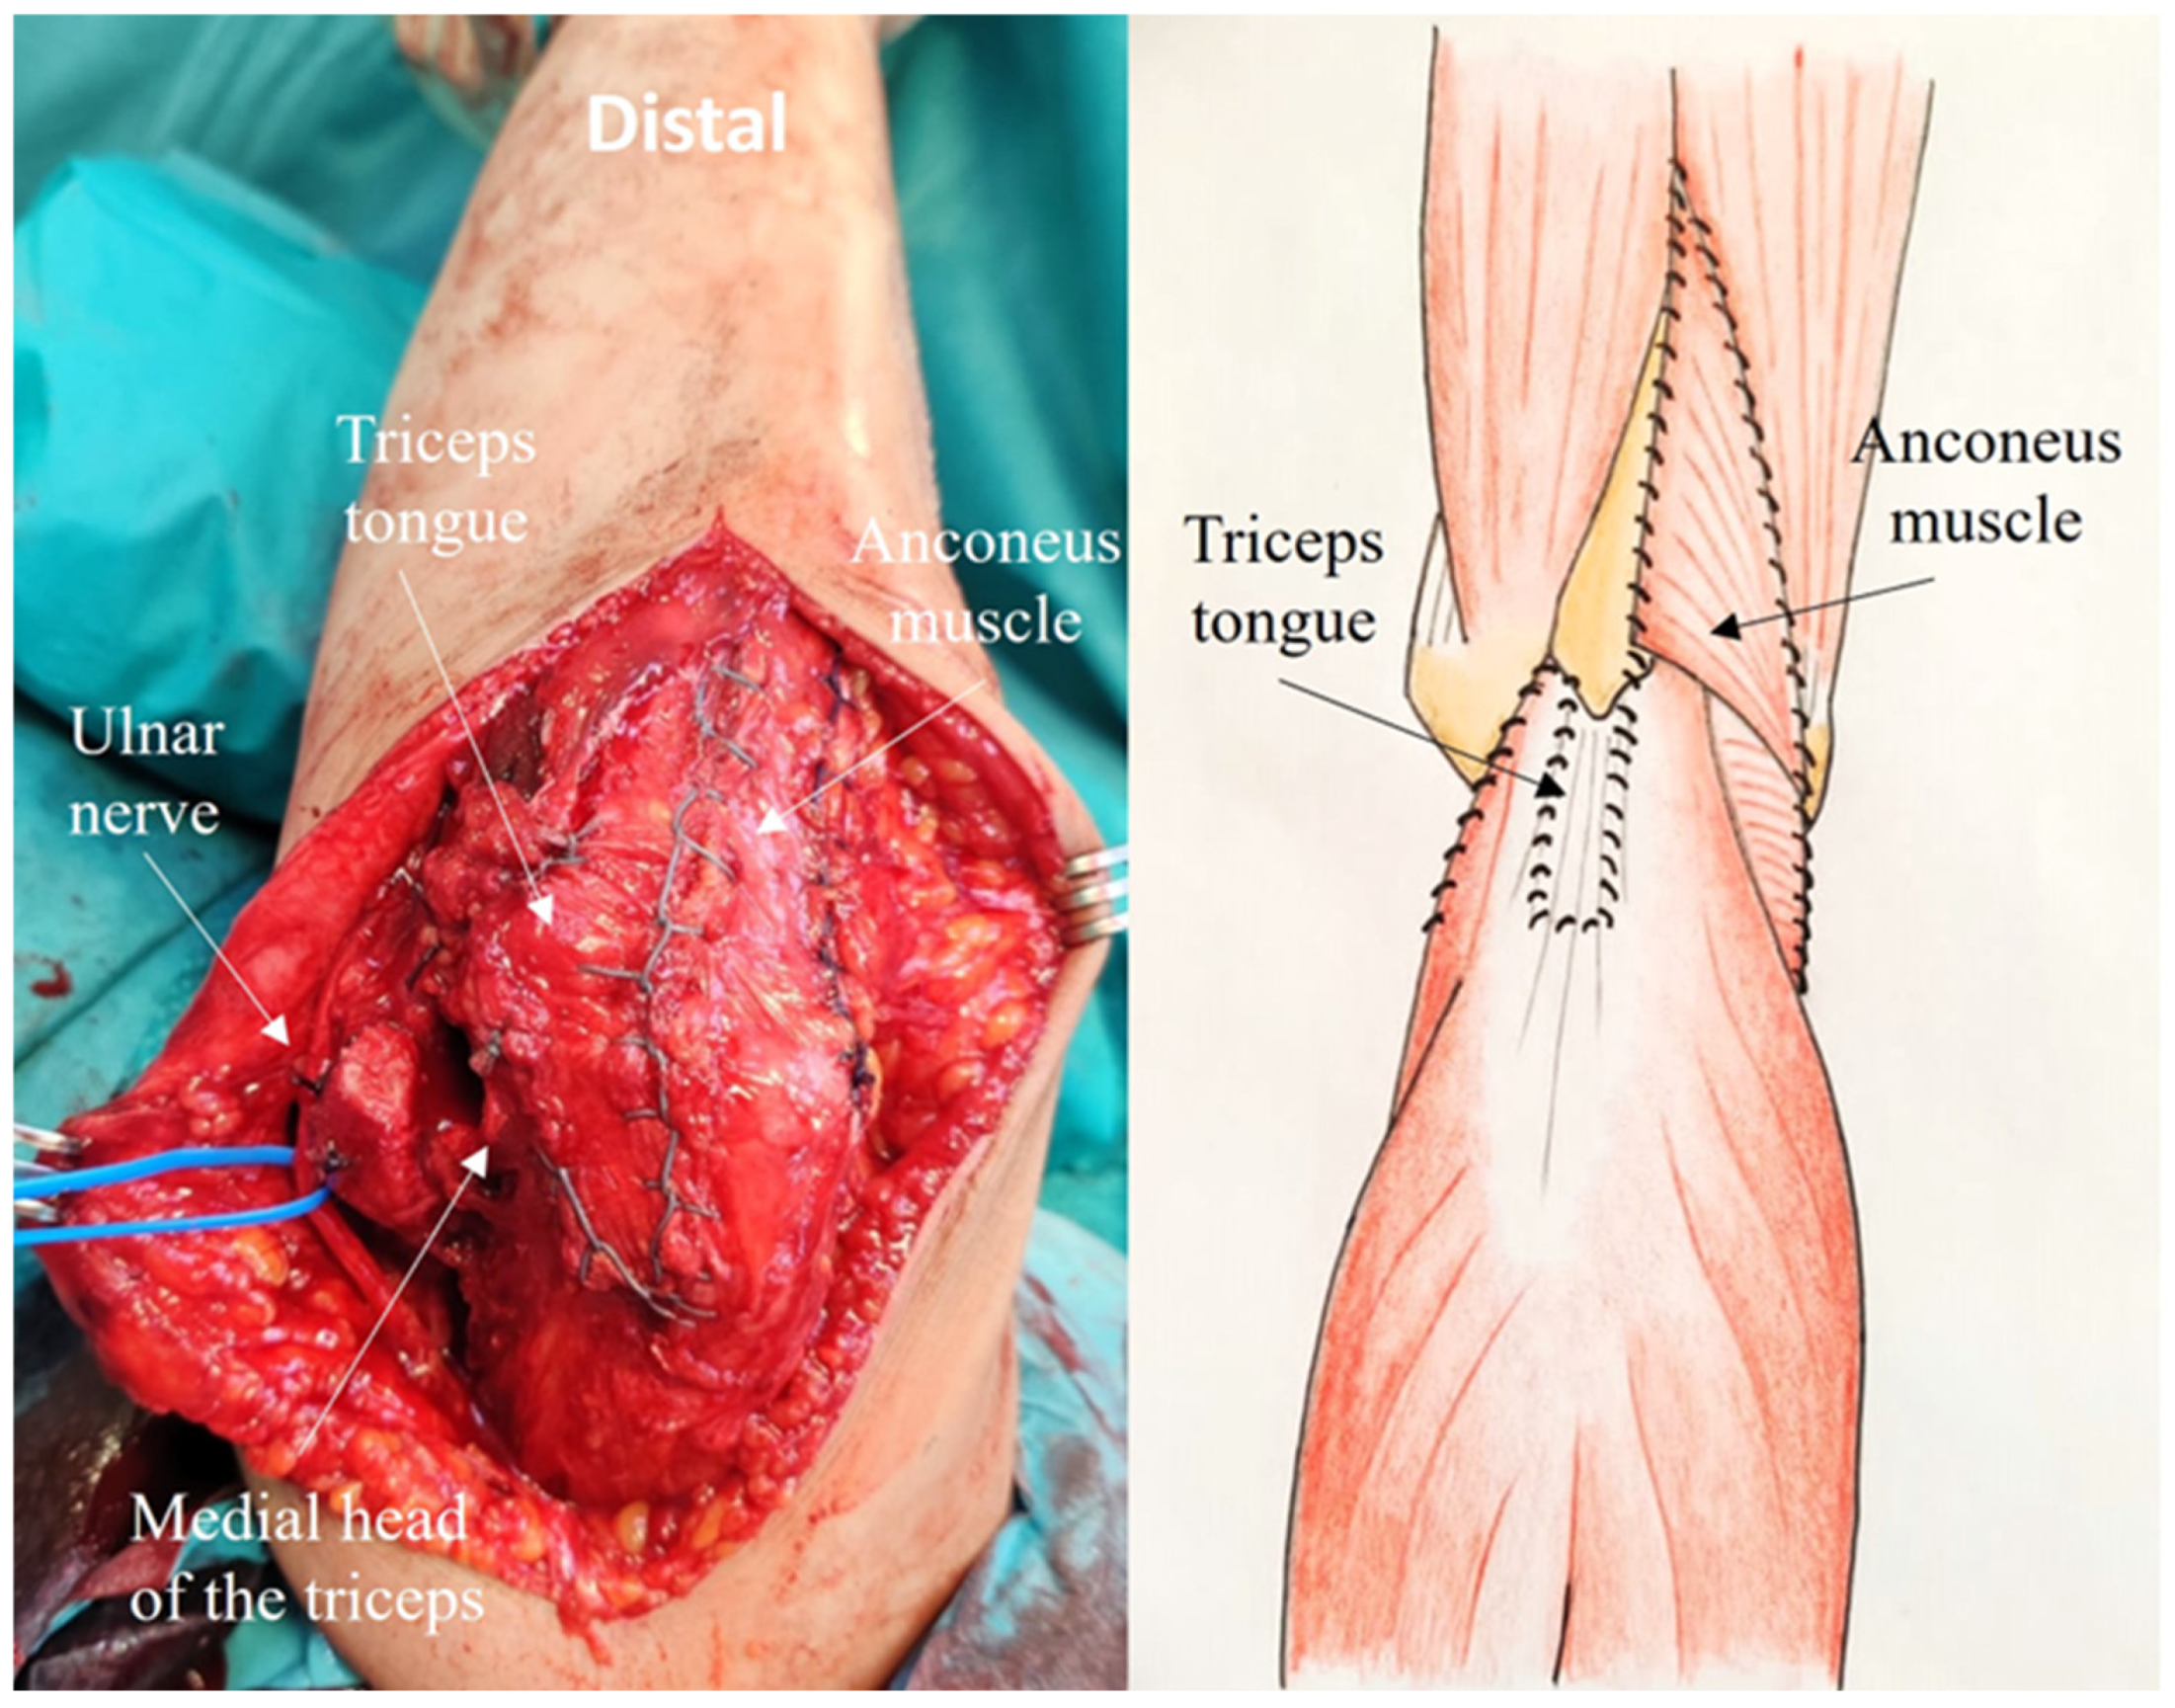

2.4. Development of the ARTT Approach